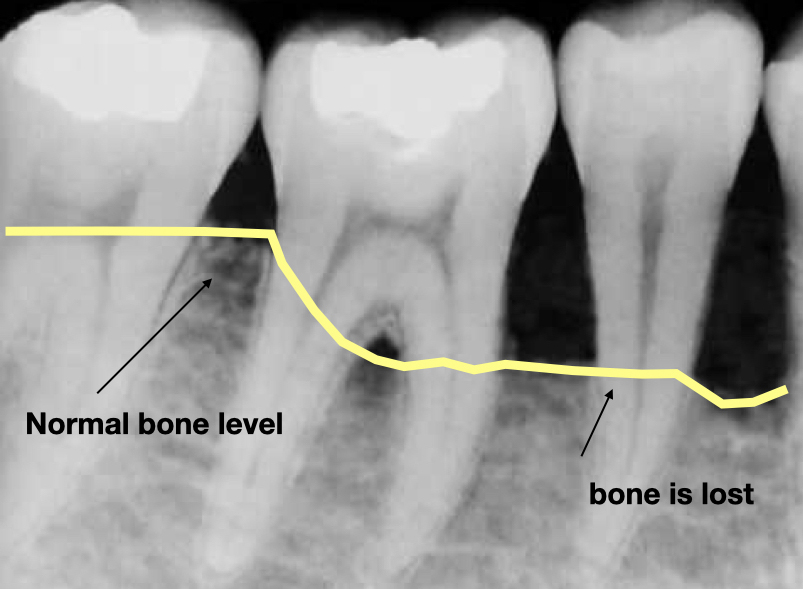

Zahnfleischtaschen sind die ideale Umgebung für das Bakterienwachstum (37 ° C, feucht und anaerob (kein Sauerstoff)). Sie können unmöglich zu Hause gereinigt werden. Je tiefer die Tasche (z.B. 6 mm), desto höher ist die Bakterienbelastung. Mit jeder Mahlzeit, die Sie zu sich nehmen, sammeln sich in diesen Taschen mehr Nahrungsmittel, die die Bakterien zusätzlich ernähren und so das weitere Wachstum unterstützen. Wenn die bakterielle Belastung zunimmt, nimmt der Knochen um Ihre Zähne ab und schließlich lockern sich Ihre Zähne. Unbehandelt ist die Entfernung des Zahnes sicher.

- Eine anhaltende Zahnfleischentzündung kann Knochenentzündung verursachen, wodurch sich Taschen zwischen Ihrem Zahnfleisch und Zähnen bilden können, die sich mit Plaque, Zahnstein und Bakterien füllen. Mit der Zeit werden diese Taschen tiefer und füllen sich mit mehr Bakterien. Wenn Sie nicht behandelt werden, führen diese tiefen Infektionen zu einem Verlust von Gewebe und Knochen, und letztendlich können Sie einen oder mehrere Zähne verlieren. Auch chronische Entzündungen können Ihr Immunsystem belasten.